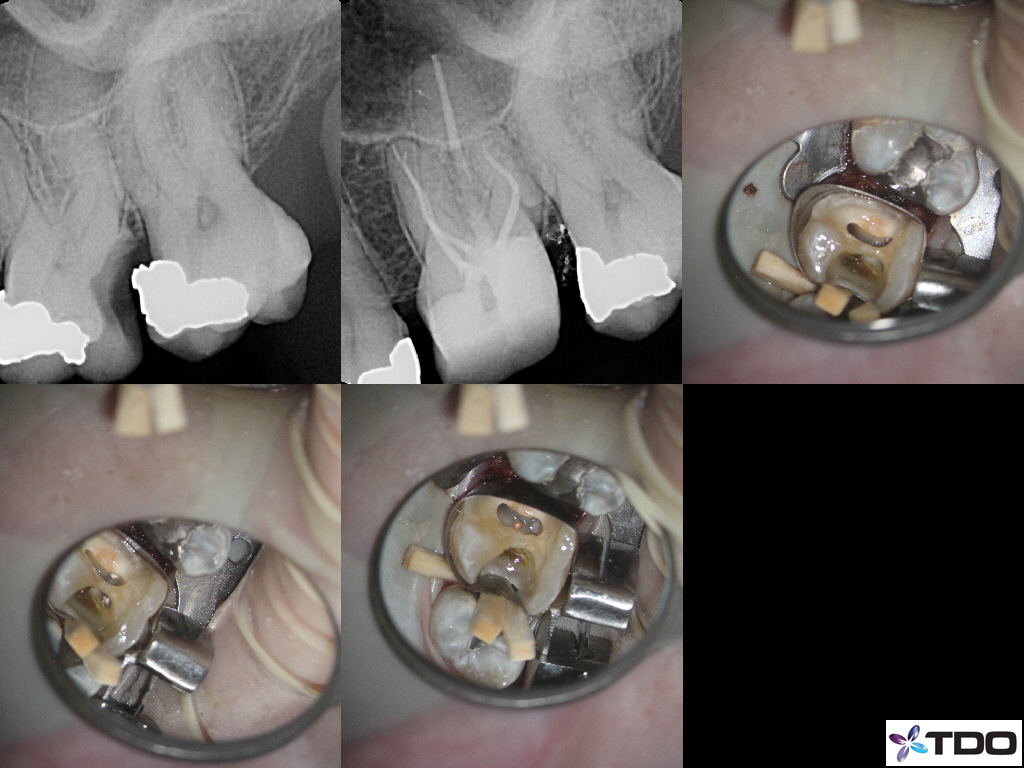

These cases show a level of commitment to conservative endodontics rarely seen in endo today. Plus the restorative excellence is inspiring and should stimulate all endodontists to up their game and help others realize how important the restorative aspect of endodontics is.